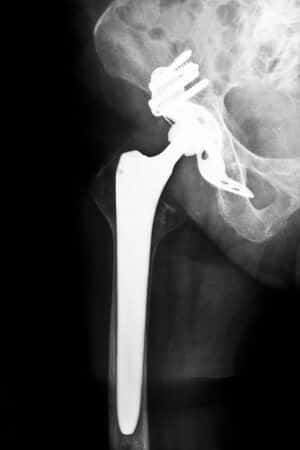

This case involves a fifty-two-year-old patient who sustained a sub-capital right hip fracture following a slip and fall. She was immediately taken to the local trauma center and underwent hip surgery by an orthopedic surgeon. The physician performed a bipolar endoprosthesis of the right hip using a ceramic Stryker Orthopaedics UHR Universal Head Bipolar Component. Following surgery, the patient complained of immediate pain, which remained during the months following the surgery. The patient’s surgeon, however, was sentenced to prison time on financial fraud charges during the course of her follow-up treatment and required the patient to seek treatment from another orthopedic surgeon. The diagnostic testing ordered by the second physician revealed that the source of the patient’s pain was the right hip bipolar prosthesis. Further investigation yielded evidence of a translucent line around the femoral prosthesis. The new surgeon suspected that loosening of the device was most likely the cause of discomfort and the patient was recommended for a total right hip revision surgery.